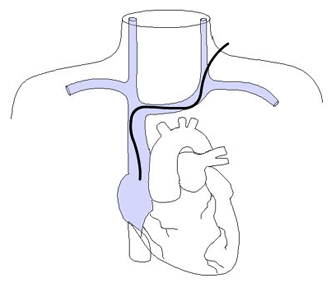

Diese Anforderungen treffen ausschließlich auf die proximale rechte Vena jugularis / Vena anonyma zu, die deshalb als Standardzugang verwendet werden sollte, zumal diese Punktion auch besonders einfach unter sonographischer Kontrolle erfolgen kann.

Die Vena jugularis/ Vena anonyma kann nach Yoffa zwischen medialem und lateralem Kopf des Musculus sternocleidomastoideus von ventral punktiert werden oder horizontal von lateral. Diese Methode wurde 1972 von den amerikanischen Herzchirurgen Garcia, Mispireta und Pinho nach ausführlichen anatomischen Präparationen als einfachster und ungefährlichster Zugang beschrieben. Das Zielgebiet, der Zusammenfluß von Vena jugularis und Vena subclavia zur Vena anonyma ist so groß, dass die Punktion auch ohne Sonographie immer beim ersten Stich gelingt.

Langzeitkatheter und Portkatheter werden von der Punktionsstelle supraklavikulär 4 - 6 cm bis zum Thorax tunneliert.

Da tunnelierte Katheter eine fixe Länge haben, muß die Austrittsstelle exakt vermessen werden, dass einerseits die Katheterspitze im Vorhof bzw. der Vena cava superior liegt, andererseits der Tefloncuff mindestens 2 cm von der Austrittsstelle entfernt im Tunnel.

Vor der Einmündung in die Vena anonyma macht die Jugularvene einen Knick von 45 Grad nach dorsal. Diatator, Einführschleuse und Katheter stoßen dort an der Venenvorderwand an und erzeugen Intimaläsionen, die bei 30% der Patienten später zur Thrombose führen.

Von links eingeführte Katheter stoßen in der in mehreren Ebenen gewundenen Vena brachiocephalica an die Venenwand an und verursachen Intimaläsionen und Thrombosen. Die Wandschäden sind umso schlimmer, je steifer der Katheter ist. Die schlimmsten Schäden rufen die in der Intensivmedizin üblichen lage bore Katheter hervor.

Etwa 10% der Bevölkerung haben als embryologisch bedingte Anomalie eine links persistierende obere Hohlvene, die meist in den Sinus coronarius mündet. Liegt ein von links eingebrachter Katheter im Sinus coronarius, dem venösen Abfluß des Herzens, kann die Infusion hochosmolarer Ernährungslösungen oder irritierender Zytostatika zu einer akuten Sinusthrombose mit Behinderung des venösen Abflusses aus dem Myokard führen. Der Anstieg des myokardialen Perfusionsdruckes führt zu einer Ischämie auch bei gesunden Koronararterien mit Infarkten, Arrhythmien und plötzlichem Herztod (W Masood, KK Sitammagari: Coronary Sinus Thrombosis. StatPearls Publishing; 2020 ).